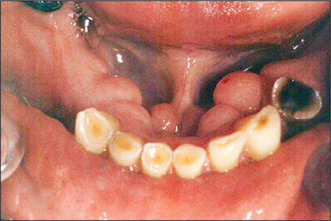

Most patients tolerate the loss of their natural teeth and subsequent denture wearing without difficulty. However, there may be extensive loss of alveolar bone after tooth extraction, resulting in an atrophic (flat or knife-edged) edentulous ridge (Fig. 11.4). In some patients this can make denture wearing difficult or uncomfortable. The prosthodontist may be able to modify a denture design to enhance its stability and retention, but this is not always possible. Surgery may therefore be required to enhance retention and stability of the prosthesis.

image

Fig. 11.4 This 32-year-old patient has difficulty in wearing a denture. The alveolar ridge has a ‘knife-edge’ profile, and there is a loss of sulcus depth.